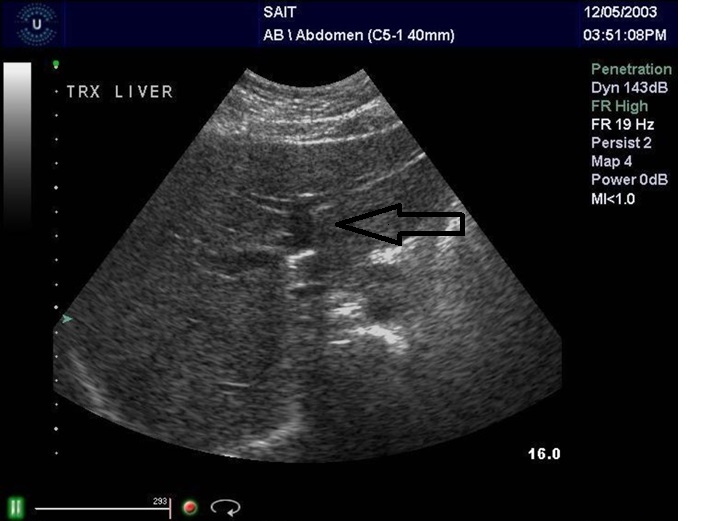

Q

From the left to right label the structures

A

1. Middle hepatic vein

2. Right portal vein the gallbladder is beside it and the gallbladder is a right structure

3. Right renal Artery